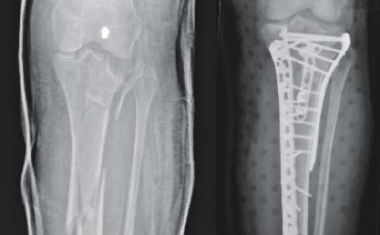

Eine neue Generation intelligenter Implantate soll direkt am Knochen überwachen, ob Schienbeinbrüche heilen. Bei Bedarf sollen sie den Heilungsprozess über gezielte Bewegung direkt an der Bruchstelle aktiv anregen.

Implantate, die bei Brüchen die Knochenteile fixieren, sollen selbst die Heilung permanent überwachen und gezielt fördern – etwa mit Mikro-Massagen an der Bruchstelle.